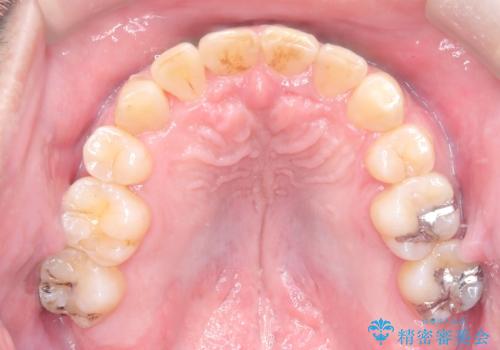

- 主訴:噛み合わせが反対になっているのを治したい

反対咬合と叢生改善のため、上下左右4番目の歯を抜歯し、審美装置にて矯正治療を行いました。

骨格性Ⅲ級を示しましたが、構成咬合位がとれたことから反対咬合と叢生改善のため、上下左右第一小臼歯を抜歯しワイヤー矯正を行いました。途中、バイトアップを行っています。